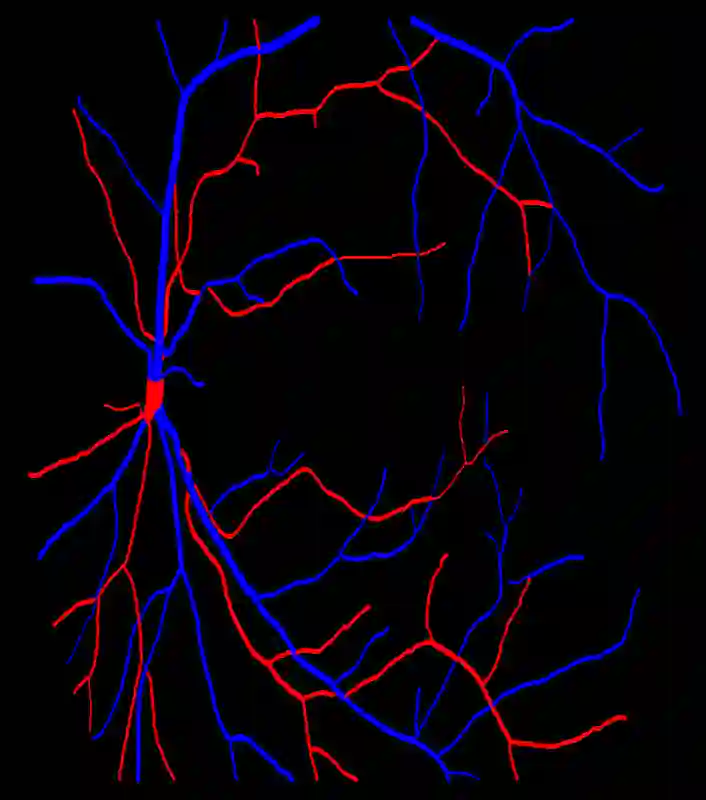

Retinal artery/vein (A/V) classification is a critical technique for diagnosing diabetes and cardiovascular diseases. Although deep learning based methods achieve impressive results in A/V classification, their performances usually degrade severely when being directly applied to another database, due to the domain shift, e.g., caused by the variations in imaging protocols. In this paper, we propose a novel vessel-mixing based consistency regularization framework, for cross-domain learning in retinal A/V classification. Specially, to alleviate the severe bias to source domain, based on the label smooth prior, the model is regularized to give consistent predictions for unlabeled target-domain inputs that are under perturbation. This consistency regularization implicitly introduces a mechanism where the model and the perturbation is opponent to each other, where the model is pushed to be robust enough to cope with the perturbation. Thus, we investigate a more difficult opponent to further inspire the robustness of model, in the scenario of retinal A/V, called vessel-mixing perturbation. Specially, it effectively disturbs the fundus images especially the vessel structures by mixing two images regionally. We conduct extensive experiments on cross-domain A/V classification using four public datasets, which are collected by diverse institutions and imaging devices. The results demonstrate that our method achieves the state-of-the-art cross-domain performance, which is also close to the upper bound obtained by fully supervised learning on target domain.